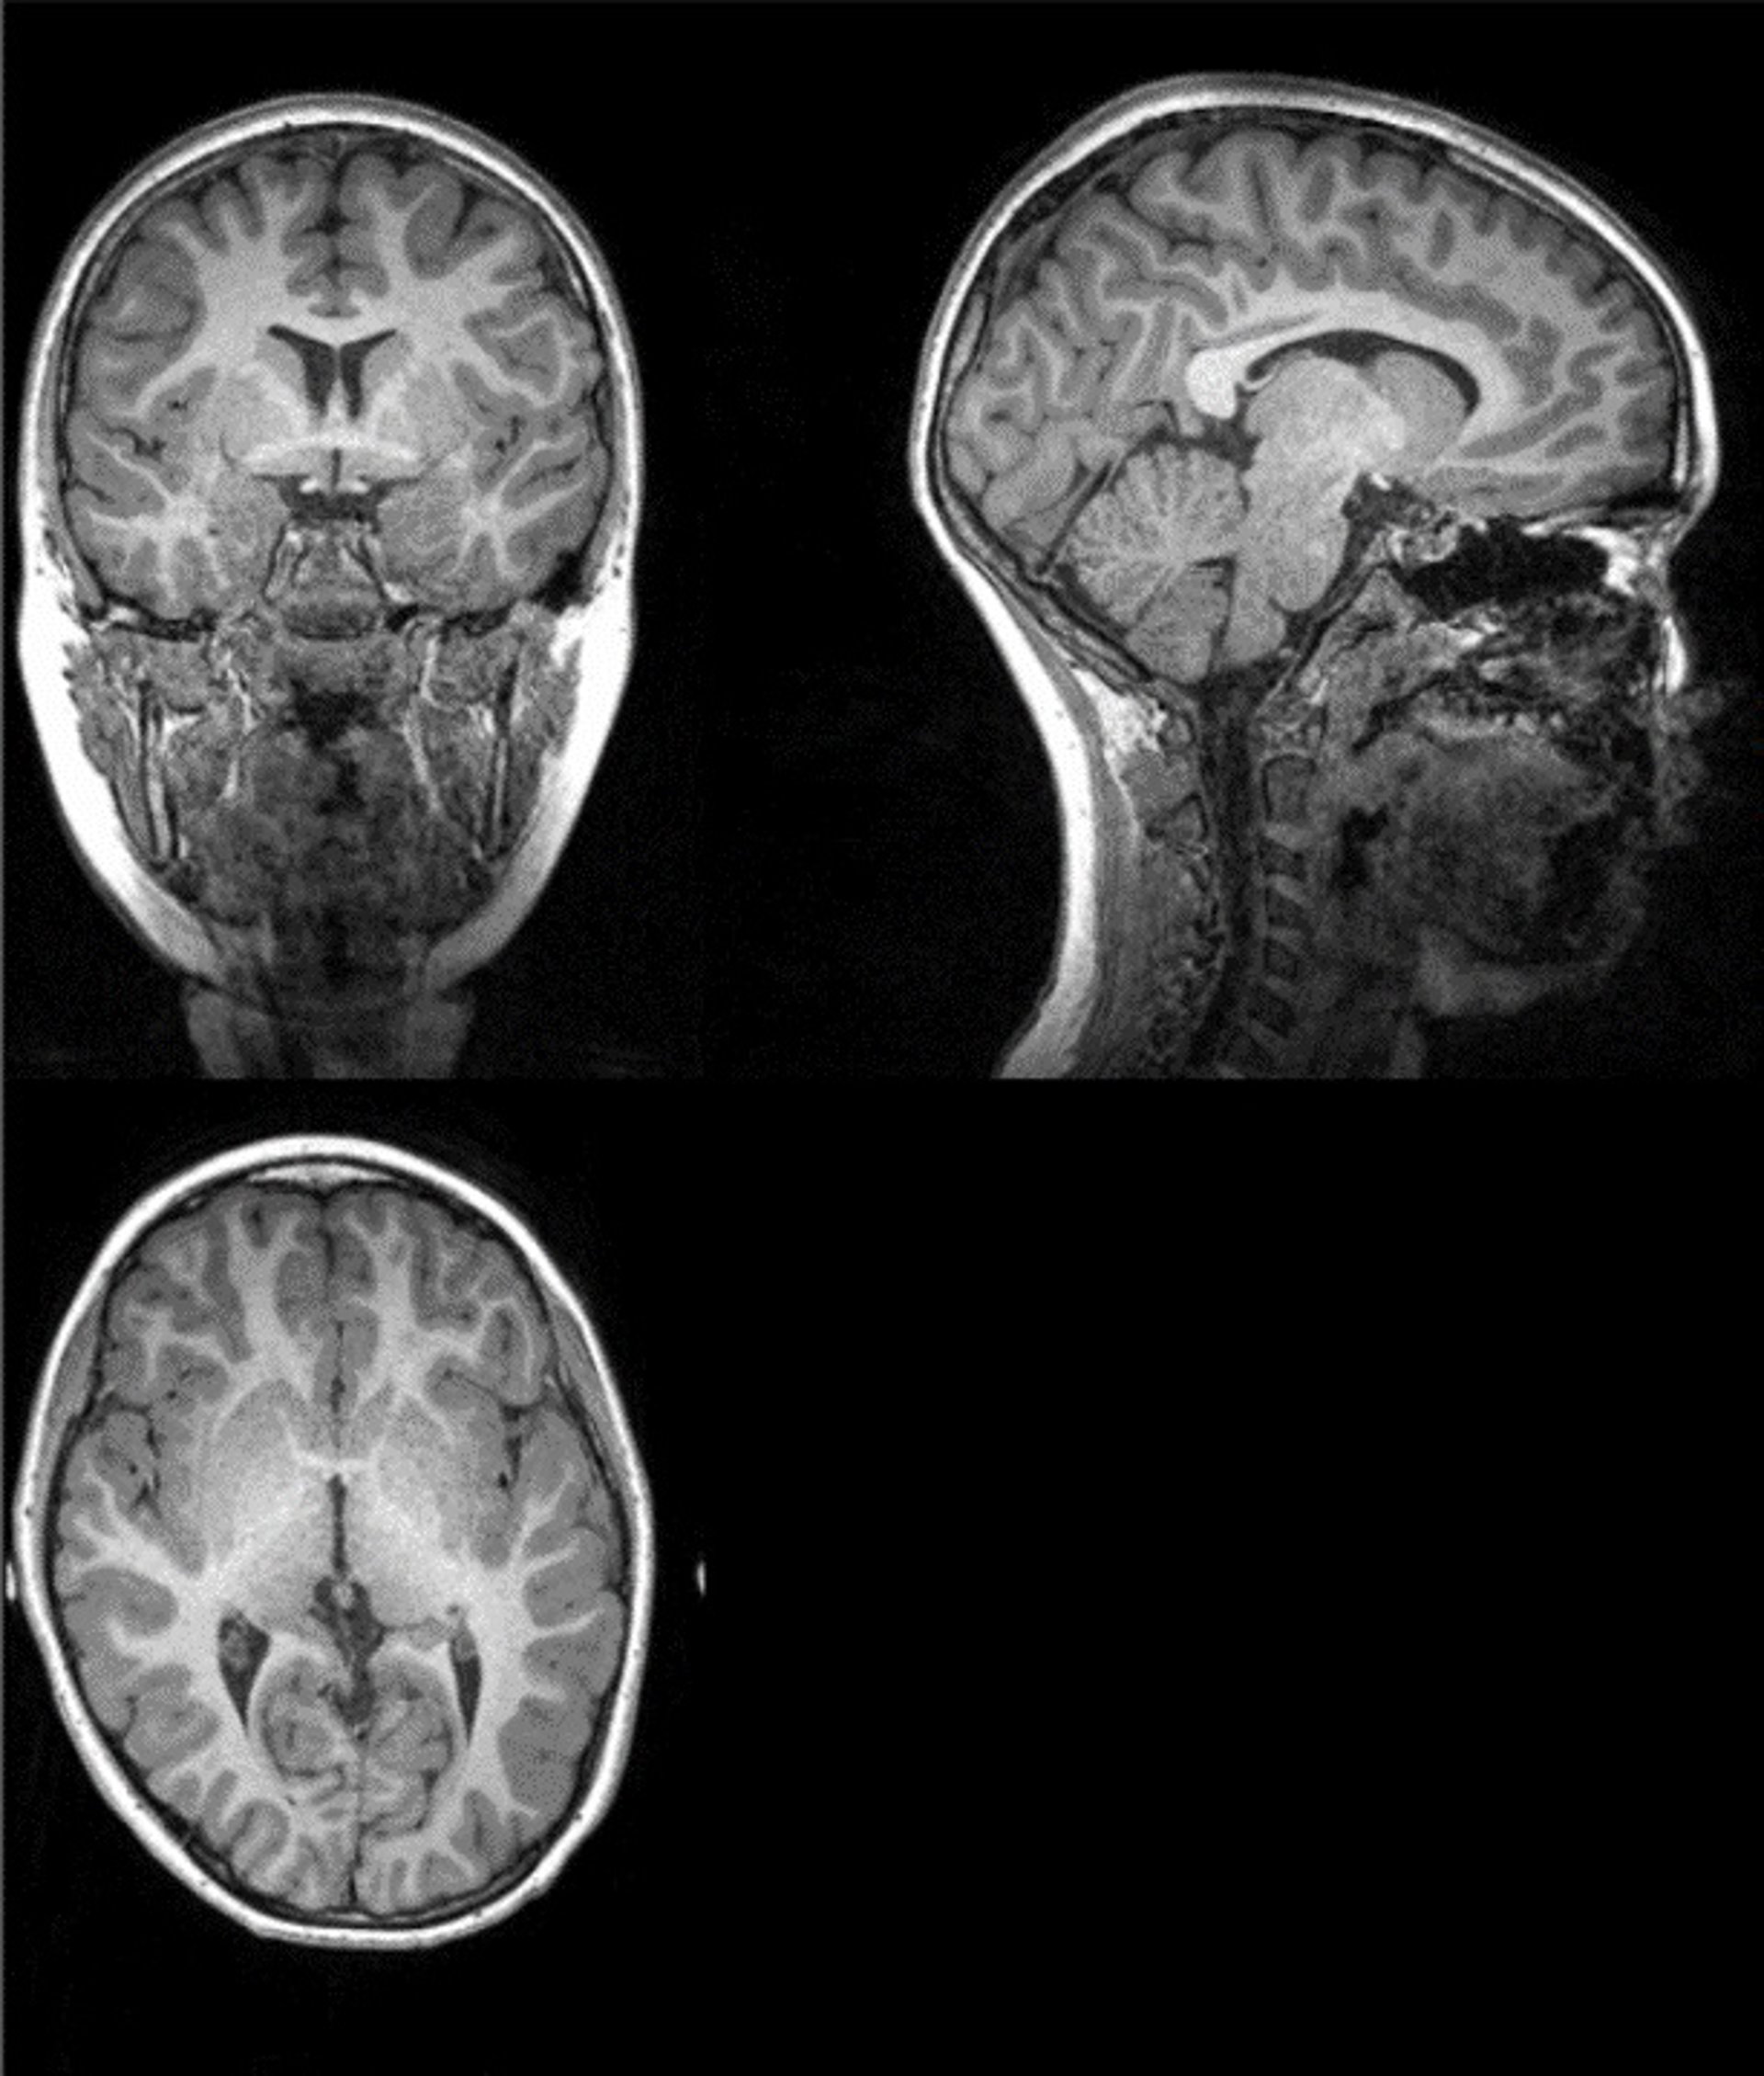

Archivo - Ejemplo de imagen original de la resonancia magnética a partir de la cual investigadores de la UGR han extraído la cantidad total de materia gris, materia blanca, y cantidad total cerebral

Archivo - Ejemplo de imagen original de la resonancia magnética a partir de la cual investigadores de la UGR han extraído la cantidad total de materia gris, materia blanca, y cantidad total cerebral - UGR - Archivo

Los investigadores analizaron tomografías computarizadas en 120 pacientes neurológicos, incluidos 58 con COVID-19 agudo y 62 sin COVID-19, emparejados por edad, sexo y enfermedad. El trabajo se realizó conjuntamente con Enrico Premi y sus colegas de la Universidad de Brescia (Italia), que proporcionaron los datos para el estudio. Utilizaron un análisis de morfometría basado en la fuente, que aumenta la potencia estadística de los estudios con un tamaño de muestra moderado.